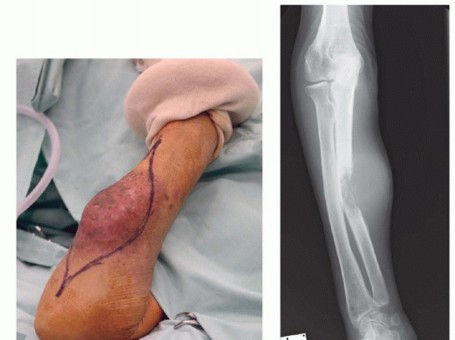

Jacob Bickels Yair Gortzak Yehuda KollenderMartin M. Malawer]Tumors of the upper extremity may cause extensive soft tissue and bone destruction and extend into the main neurovascular bundle. In those extreme situations, limb sparing may not be feasible, and amputation is required to achieve wide margins of resection and local tumor control.Above-elbow amputations may be required for advanced soft tissue and bone sarcomas of the forearm and around the elbow (FIG 1A); below-elbow amputations are performed for such tumors of the forearm and the hand (FIG 1B).Above- and below-elbow amputations are rarely done because the upper arm, elbow, and forearms are rare location for musculoskeletal tumors and because tumors at that site are noticed in relatively early stages and in most cases are resectable. Furthermore, administration of preoperative chemotherapy and availability of isolated limb perfusion have allowed to control the majority of patients that present with a large tumor.Nonetheless, above- and below-elbow amputations retain a definitive role in the management of soft tissue and bone tumors of the upper extremity.

FIG 1 • A. Above-elbow amputations are done for advanced soft tissue and bone sarcomas of the forearm. Skin incisions and osteotomy sites for metaphyseal (high), diaphyseal, and supracondylar above-elbow amputations. B. Below-elbow amputations are done for advanced soft tissue and bone tumors of the forearm and hand. Skin incision and osteotomy site for below-elbow amputation. High above-elbow amputations are those proximal to the deltoid tuberosity. Patients who undergo amputation proximal to the insertions of the deltoid and pectoralis major muscles have far greater difficulties adjusting to their prosthesis than do those who have undergone a more distal amputation.Below-elbow amputations should preserve the maximal length of both radius and ulna. Although tumors of the hand are treated by a standard below-elbow amputation, performed through the distal third of the forearm, tumors of the distal forearm require a higher amputation and warrant special consideration. A minimum of 2.5 to 3 cm of bony stump, measured from the radial tuberosity, is required to preserve function. Additional length in a very short stump can be obtained by releasing the biceps tendon; adequate flexion of the stump will be provided by the brachialis muscle.